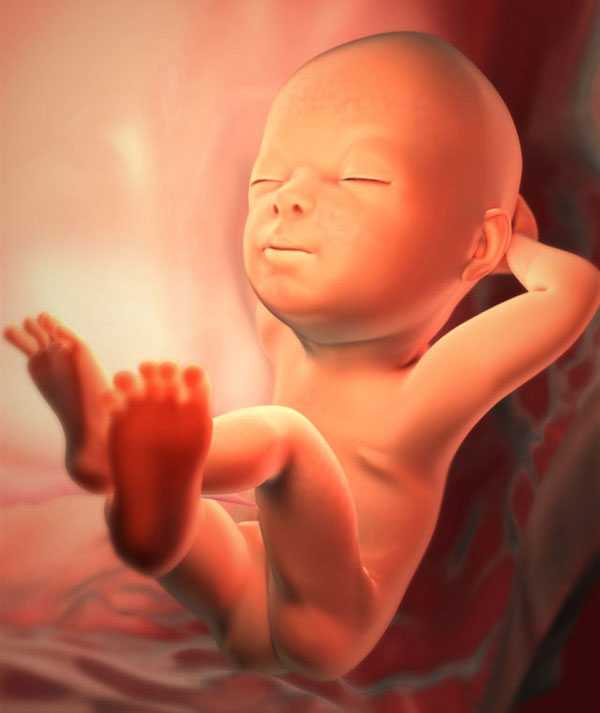

Начиная с этой недели малыш начинает набирать вес за счет того, что у него идет быстрое накопление прослойки подкожного жира. На сроке двадцати девяти недель ребенка можно сравнить со средним кочаном капусты. Он весит 1250 граммов, а его рост составляет 37 сантиметров. На данном этапе ему становится тесновато в матке, а ведь еще несколько месяцев назад он могу свободно кувыркаться, ворочаться и двигаться с одного края своего домика в другой.

На двадцать девятой неделе продолжает совершенствоваться ЦНС и ее главный орган – головной мозг. Малыш уже может не только воспринимать, но и запоминать всю поступающую к нему информацию. На данном этапе он хорошо реагирует на звуки и свет, различает вкус заглатываемой амниотической жидкости. Ученные, исследующие внутриутробное развитие, утверждают, что ребенок уже может видеть и видит сны.

Если раньше тело крохи покрывал пушок и первородная смазка, то сейчас они начинают постепенно исчезать, так как выполняемая ими защитная функция становится не нужна. Практически четыре процента от всего веса ребенка приходится на подкожный жир, который отвечает за контроль теплообменных процессов в его маленьком организме.

Сейчас кроха просто растёт и закрепляет более ранние достижения. Наиболее активно продолжается развитие подкожного жира, причём не только обычного, который есть у любого человека. У плода формируется ещё особый бурый жир. Когда малыш родится, это вещество отлично защитит его от холода. Это важно, поскольку теплорегуляция у новорождённых налаживается не сразу.

Кроме того, продолжается формирование зубной эмали на зачатках молочных зубов. По-прежнему активно минерализуется скелет плода. На это необходимо примерно 250 мг кальция каждый день. Так что есть молочные продукты вам нужно каждый день. Если кальция не хватает, он начинается буквально вымываться из костей мамы. Первыми затрагиваются зубы, они становятся ломкими, чувствительными. Если вы заметили у себя такой признак, срочно скажите об этом врачу. Возможно, в вашей ситуации потребуются препараты кальция.

Начиная с этого периода, Ваш крошка уже может самостоятельно регулировать температуру тела. Его костный мозг вовсю вырабатывает красные кровяные тела. Кожный покров уже не такой тонкий и очень схож с кожей новорожденного. В течение суток плод уже выделяет порядка 500 миллилитров мочи.

Сейчас на ножках и ручках появились ногти. Правда, еще совсем крошечные, потому они не выходят за пределы пальчиков. Происходит регулярное увеличение веса, щечки круглеют.

Первые нательные волосы – лануго – постепенно пропадают. Малыш продолжает тренировать мимику – улыбается, щурит глазки, корчит рожицы, показывает язычок.

Ребенок продолжает набирать массу тела и совершенствовать внешний вид. Уже через неделю он отправит маму в декретный отпуск, потому что работать с таким животом станет совсем тяжело. На 29 неделе малыш весит около 1250 грамм, а рост его составляет 37 см.

Третий триместр уже начался, и организм ребенка продолжает совершенствоваться в своих функциях. Развитие на 29 неделе достигает таких умений:

На этом сроке организм крошечного малыша и дальше продолжает активно развиваться и осваивать новые возможности. Организм научился контролировать температуру тела, за счет активной выработки лейкоцитов и тромбоцитов происходит процесс становления иммунитета у ребенка. Выработка жировых тканей у малыша теперь самостоятельно регулируемый процесс, с которым организм малыша уже отлично справляется. В этот период развития происходит наращивание эмали на зубах малыша, которые все еще спрятаны глубоко в деснах ребенка и находятся на стадии активного формирования.

Костный мозг малыша сформирован и стабильно функционирует. Иммунитет практически сформирован, также как и теплорегуляция организма. Состав крови ребенка с каждым днем успешно корректируется и уже приближен к нормальным показателям.

Внешне ребенок уже практически сформировавшийся новорожденный. Кожа малыша расправляется и очищается от большого количества смазки, полностью исчезает оставшийся пушок, лануго.

Половые органы находятся на стадии завершения своего формирования. Все последующие внутриутробные недели малыш будет активно набирать вес и рост. Сейчас же, вес малютки около 1кг 250 г, рост в среднем 38 см.